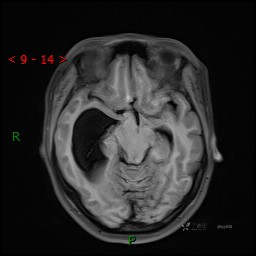

简要病史:患者于1月前无明显诱因出现视物模糊,无明显头痛头晕,无恶心呕吐,无昏迷,无肢体偏瘫等症状,就诊于当地医院头部CT考虑:右侧丘脑、脑室占位。予以对症处置后家属为求进一步诊治来我科,以“颅内占位”收入院。 起病以来,精神、饮食、睡眠欠佳,大小便正常,体力下降,体重无明显变化。

辅助检查:CT MRI

临床诊断:脑室占位

MRI平扫